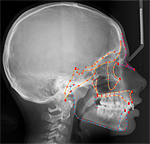

Morphing and warping: Part II. Halazonetis DJ. Am J Orthod Dentofacial Orthop. 1999 Jun;115(6):706-8. doi: 10.1016/s0889-5406(99)70098-3. PMID: 10358255

Morphing and warping. Part I. Halazonetis DJ. Am J Orthod Dentofacial Orthop. 1999 Apr;115(4):466-77. doi: 10.1016/s0889-5406(99)70074-0. PMID: 10194292